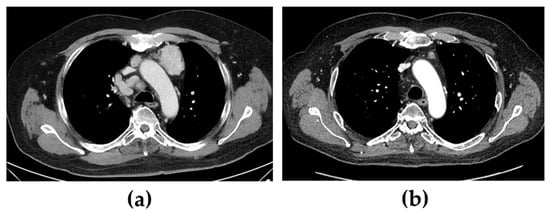

When the patient was diagnosed with Cushing’s syndrome, treatment with metyrapone (750 mg three times daily) was initiated. Two days later, s-cortisol was under the limit of detection, and hydrocortisone was added in a block-and-replacement regime. On a histopathological re-examination of the tumour, immunohistochemical staining for ACTH was positive. Four days after treatment with metyrapone was started, after an oncogenic mutation in exon 16 of the RET gene was confirmed, i.e., the most commonly affected exon in sporadic cases [5], treatment with selpercatinib (160 mg two times daily) was also initiated. At that time, the patient had several lymph node metastases, the largest being found in the mediastinum (47 × 35 mm) and between the pancreas and aorta (largest diameter was 69 mm) (Figure 1a,c). Six months later, all the cushingoid features had resolved, s-calcitonin had decreased from 580 pmol/L to 3.5 pmol/L (normal < 3), and the metastases had decreased significantly in size.

Figure 1.

Computed tomography showing mediastinal and abdominal lymph node metastases before (a,c) and 12 months after (b,d) treatment with selpercatinib was started. Of additional note is a hyperplastic adrenal gland (arrows) before treatment that decreased in volume following treatment.

After further 6 months, s-calcitonin had normalized (1.5 pmol/L), and radiological evaluation showed a profound tumour volume reduction (Figure 1b,d). Furthermore, due to the excellent biochemical and radiological response to selpercatinib, both metyrapone and hydrocortisone were discontinued without a subsequent recurrence of the hypercortisolism. In fact, the patient had instead developed adrenal insufficiency with both unstimulated and stimulated s-cortisol < 60 nmol/L, also indicating an excellent response to selpercatinib. Hydrocortisone replacement was therefore reintroduced.